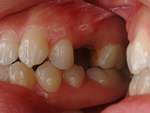

~臼歯術前~

コンポジットレジン充填

~臼歯術後~